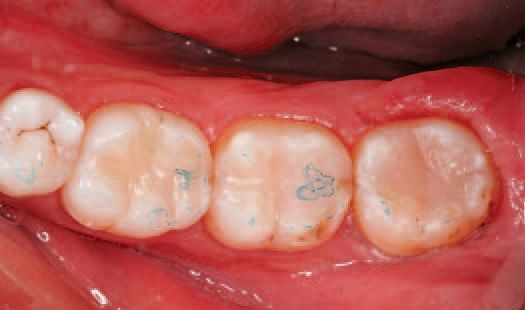

After inspecting the old amalgam restorations (Fig. 2), a rubber dam was then placed (Fig. 3). Next, using Sybron Dental’s Axis course diamond bur, KS3, the amalgam restorations and all damaged tooth structure were removed (Fig. 4).

After polishing, the rubber dam was removed, and articulating paper was used to check the patient’s occlusion (Fig. 29).

The occlusion was determined to be satisfactory and the restorations complete (Fig. 30). The patient returned the following week for a visit and reported no post-op sensitivity. After re-hydration, the excellent color-matching to the patient’s natural dentition was visible, and all three restorations appeared esthetically similar.